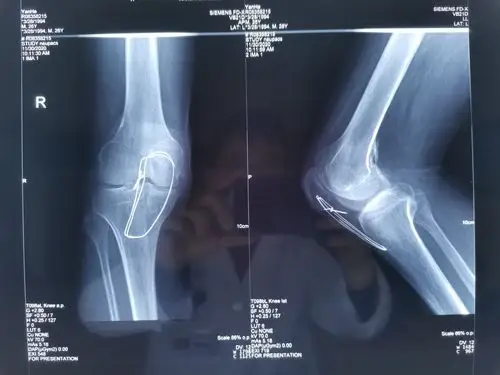

膝关节韧带,尤其是十字韧带,是最容易受伤的部位,有球场杀手之称.

髌韧带,前后交叉韧带,外侧副韧带损伤患者